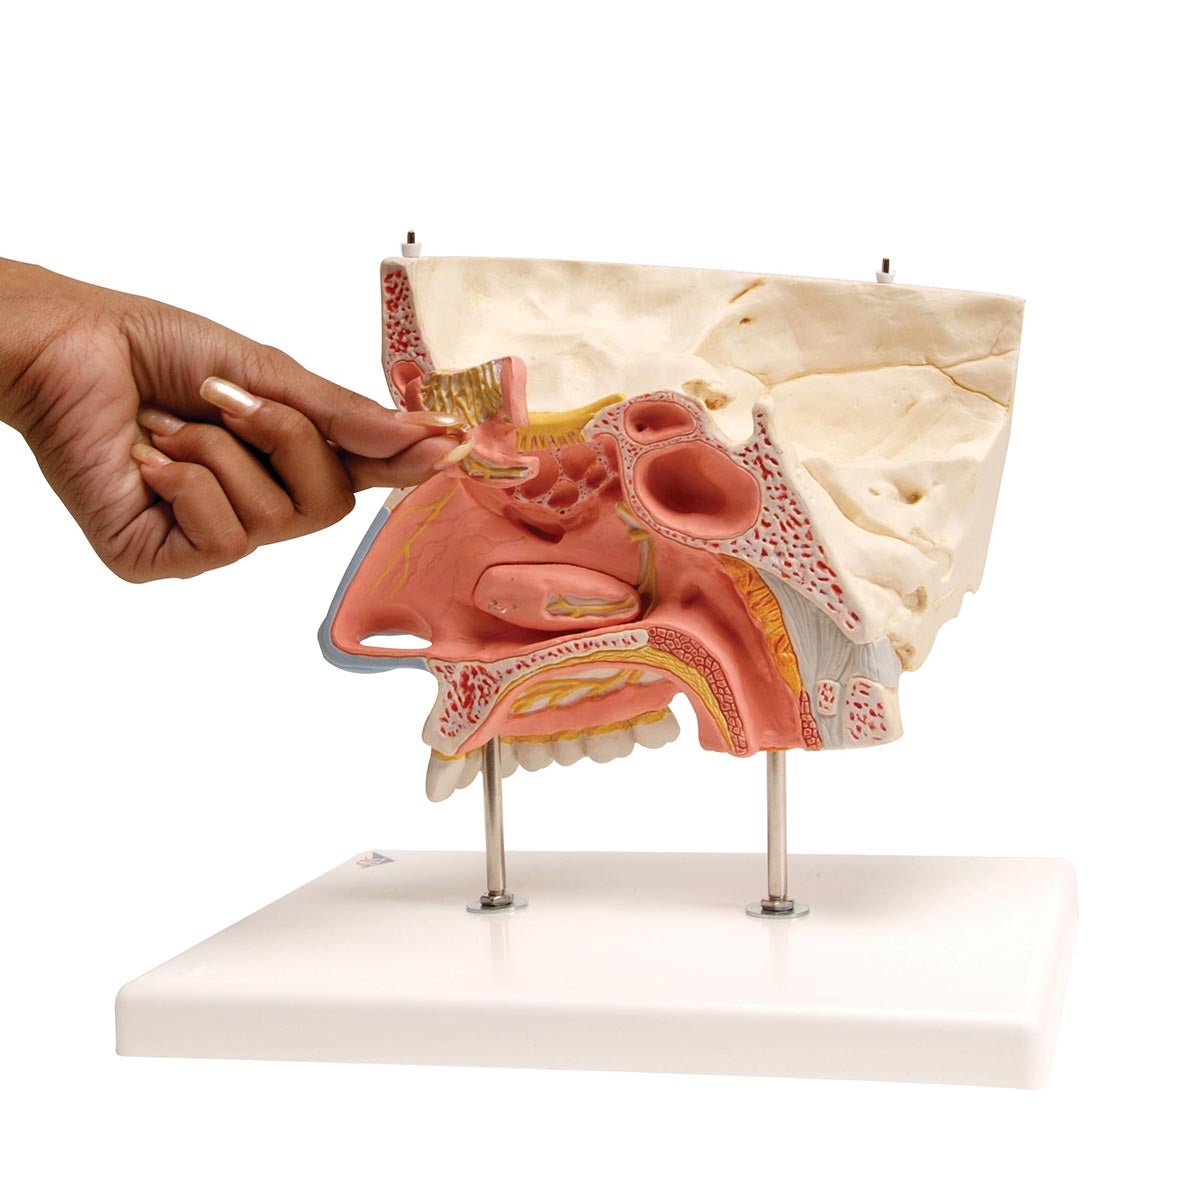

Salg af anatomiske modeller er det bærende element i eAnatomi, selvom vi også bruger mange ressourcer på at udvikle vores egne anatomiske materialer som fx plakater. Anatomiske modeller anvendes til forskellige formål og kan både vise afgrænset væv, organer samt organsystemer. Søger du en simpel model af knoglevæv eller måske en avanceret torso-model baseret på MRI teknologi, kan du finde det hele på eanatomi.com.